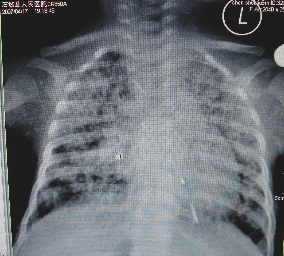

以下是引用余辉在2007-4-30 16:36:00的发言:[br]呵呵,图片不行啊,双肺弥漫斑片状影。右肺门增大,结构模糊。左侧脑室前部室管膜下可见团块状高密度影,周围有低密度环带,左额叶呈大片状低密度改变,略呈楔形,累及灰白质,局部脑沟裂消失,右额叶脑白质亦可见点状病灶(不知是伪影还是真病灶)脑室系统明显扩张,有全脑脑萎缩征象,不知其病史,暂考虑1双肺结核,左额叶结核性脑炎,(左侧脑室前部室管膜下肉芽?出血?)合并脑积水脑萎缩(左额叶低密度区不排除脑梗塞改变)2双肺非特异性炎症合并化脓性脑炎